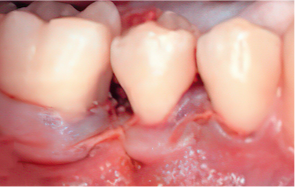

엠도게인 도포

-

STEP 05

클렌징

STEP 06

판막을 봉합

Before & After